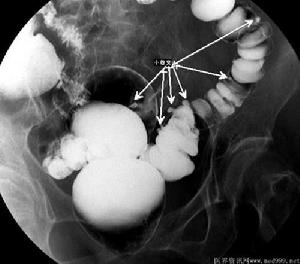

5.鋇劑灌腸

可見憩室存在或多發性憩室存在。憩室炎時見腸壁不整齊,腸管輕度漸進性狹窄。憩室炎嚴重時一般不宜做檢查,以免誘發腸穿孔。